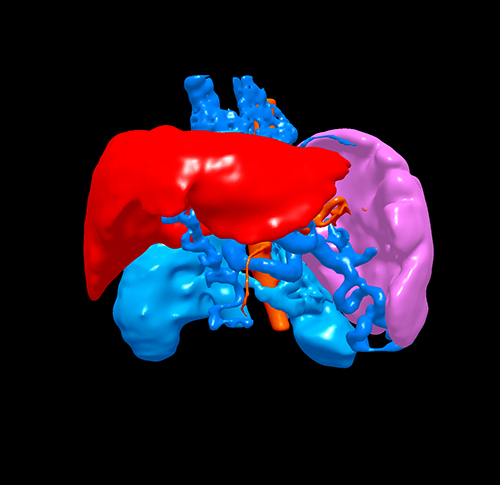

门脉高压、门静脉海绵状变、S3肝癌------S3切除、脾切除